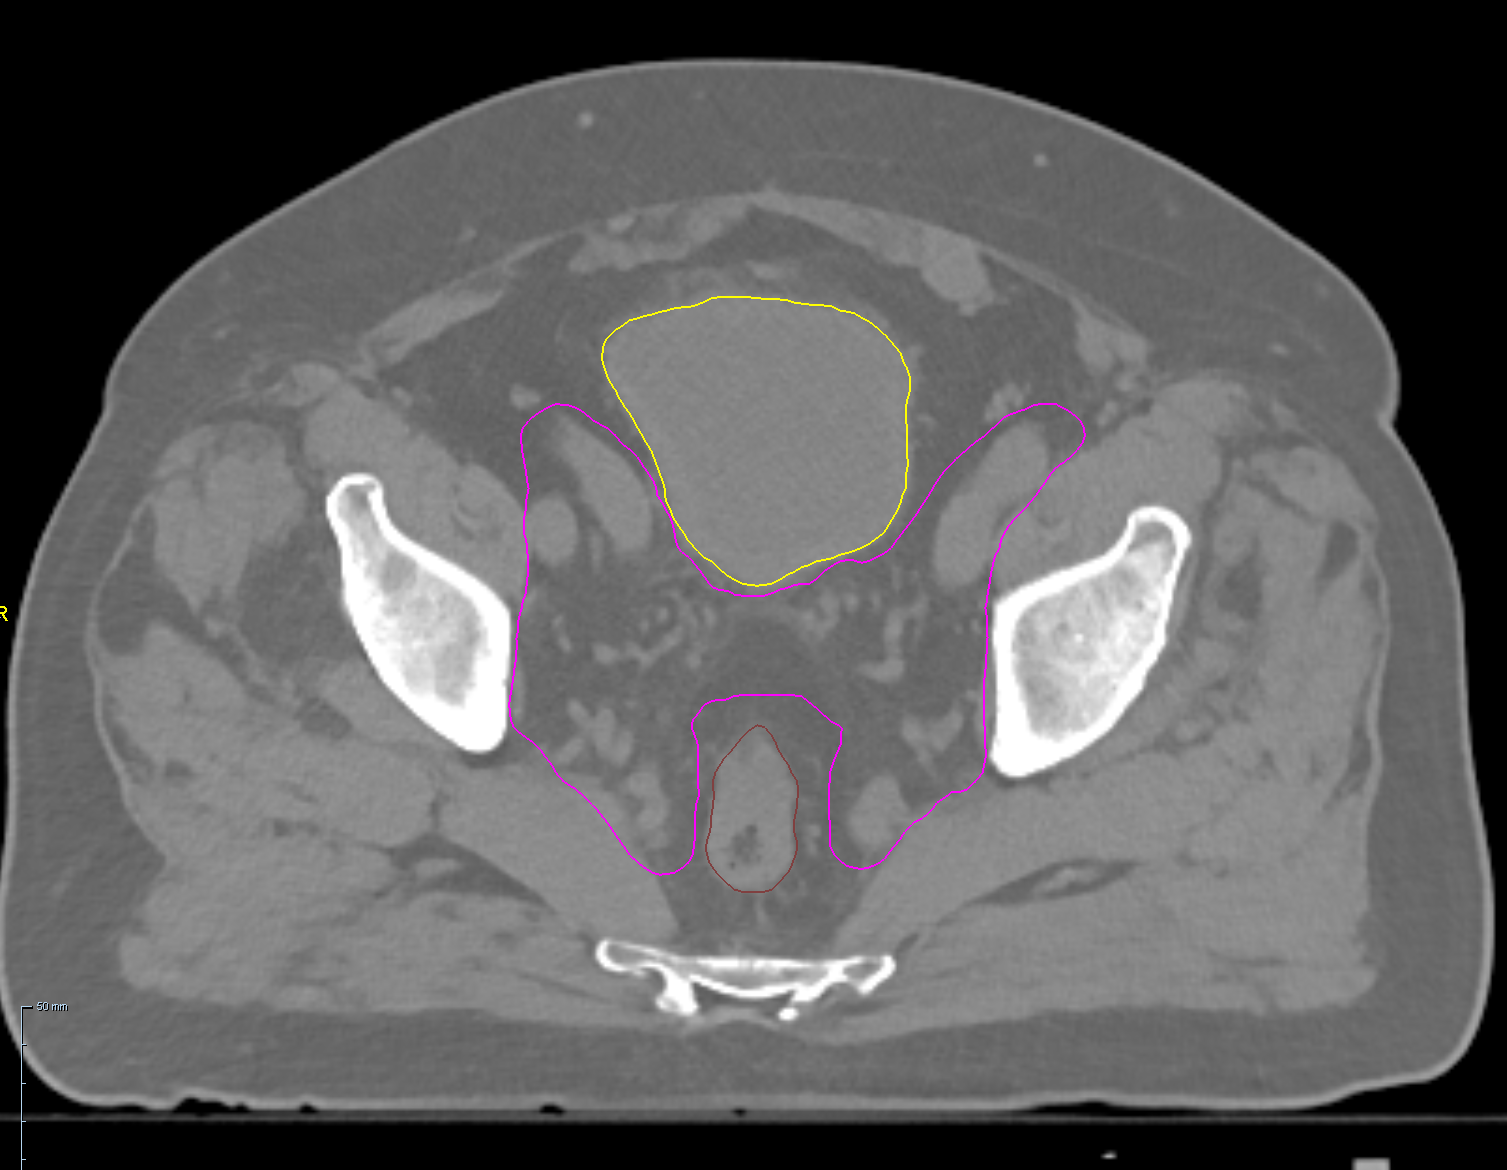

< View All Plan Studies RADIXACT SYSTEM TMI Case History AGE: 76-year-oldGENDER: Male Medical History Immidiate tolerance: Grade II dermatitis with eyelid edema, Grade I conjunctivitis resolved with Sterdex Diagnosis: Squamous cell carcinoma of the right lower eyelid Planning CT Images Treatment Plan Images ClearRT® Images Treatment Planning Highlights Fractionation